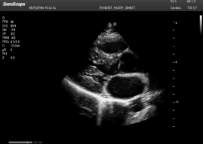

不同的探頭對(duì)應(yīng)于不同的臨床領(lǐng)域,不同的探頭頻率也應(yīng)用于不同的人體組織。超聲波在人體中的衰減與探頭頻率有關(guān),探頭頻率越高,穿透力越弱,分辨率越高,而探頭頻率越低,穿透力越強(qiáng),分辨率越低。因此在檢查淺表器官時(shí)應(yīng)選用高頻探頭,而檢查深部臟器時(shí)則選用穿透性強(qiáng)的低頻探頭。